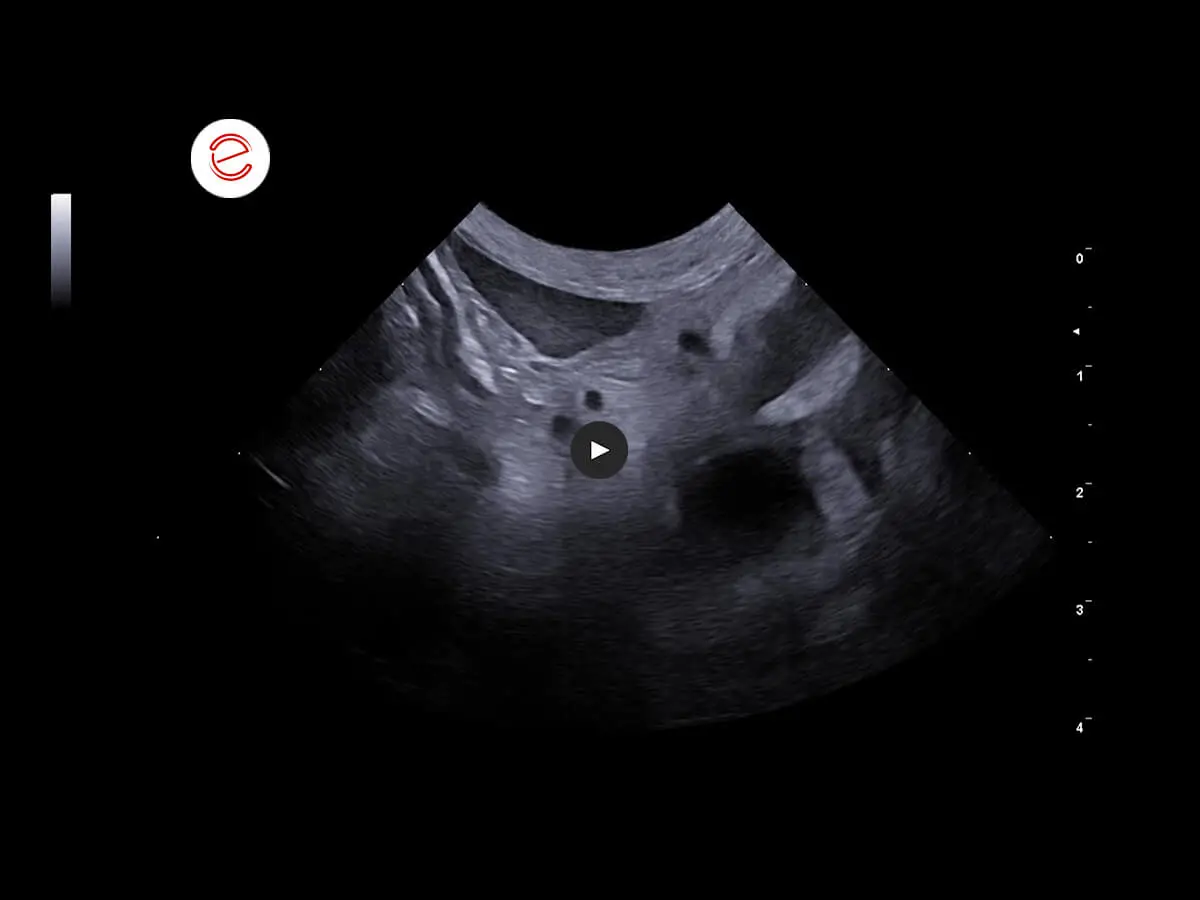

Right kidney: dimensions increased. Margins normal. No cortico-medullary distinction. Diffuse hypo-anechogenicity with findings of a hyperechoic band in which radially developing hyperechoic areas were reported.

The alterations in the right kidney are compatible with a neoplastic infiltrative process in a differential diagnosis with hydronephrosis secondary to a severe inflammatory process. Alterations in the left kidney consistent with severe nephropathy associated with findings of calcifications in differential diagnosis with lithiasis. Diffuse peritonitis also observed. Cytological examination of the right kidney recommended.